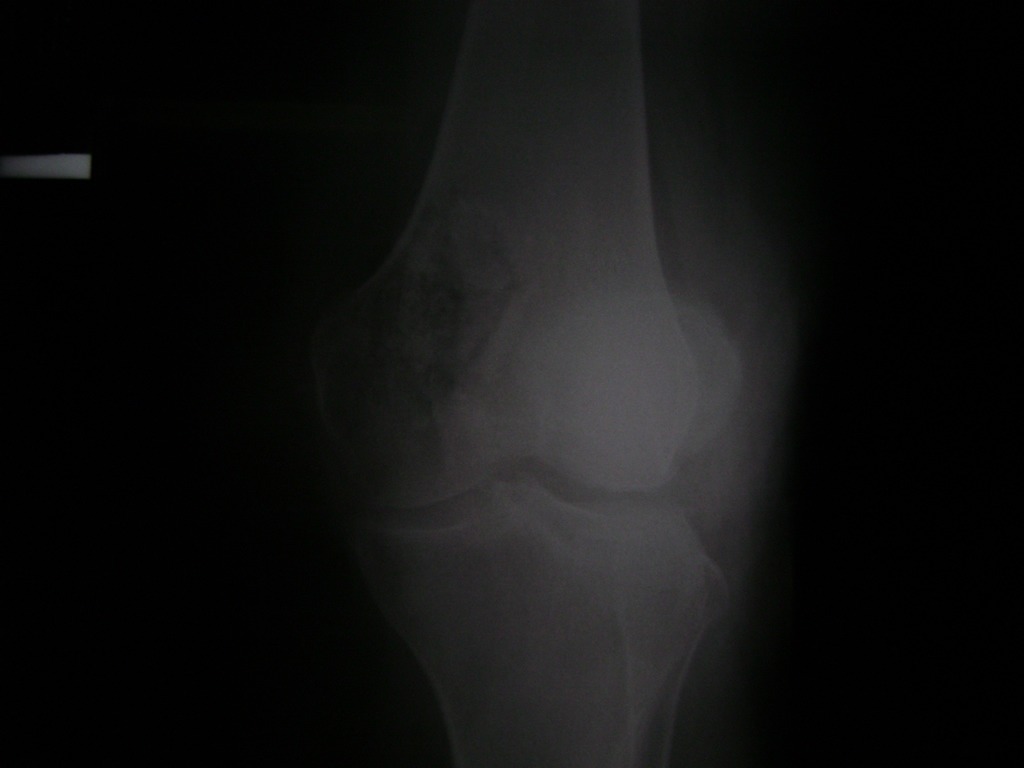

Cirugía de Tibia y Peroné

La artroscopia de rodilla es un cirugía en el cual la estructura interna de la articulación es examinada ya sea para realizar un diagnostico o para realizar un tratamiento, este procedimiento se realiza utilizando un instrumento parecido a un pequeño tubo llamado artroscopio.